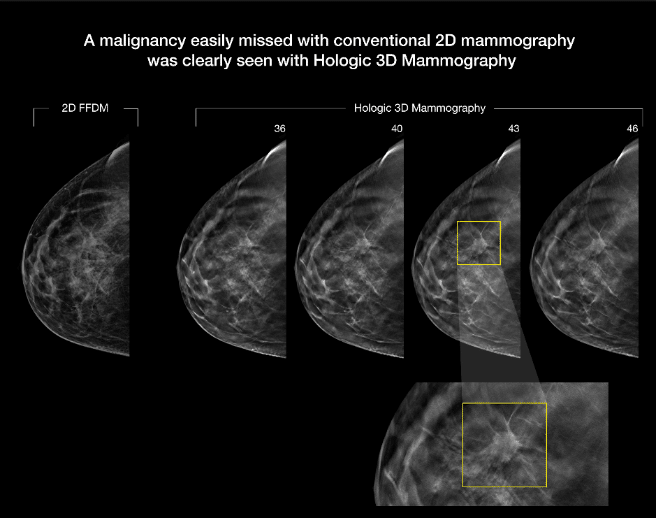

The Selena Dimensions system’s 3D Mammogram exam offers the best breast tomosynthesis technology that is proven to detect 20%-65% more invasive breast cancers compared to 2D alone. The FDA has approved this as superior for women with dense breast tissue. 3D mammography has proven to reduce callbacks by up to 40%, compared to 2D alone.

Our state of the art Hologic, Selena Dimensions mammogram unit captures 3D images of the breast, making screening more reliable. The best part? Harrison County includes 3D images for every screening mammogram we do, offering the best care to our community.